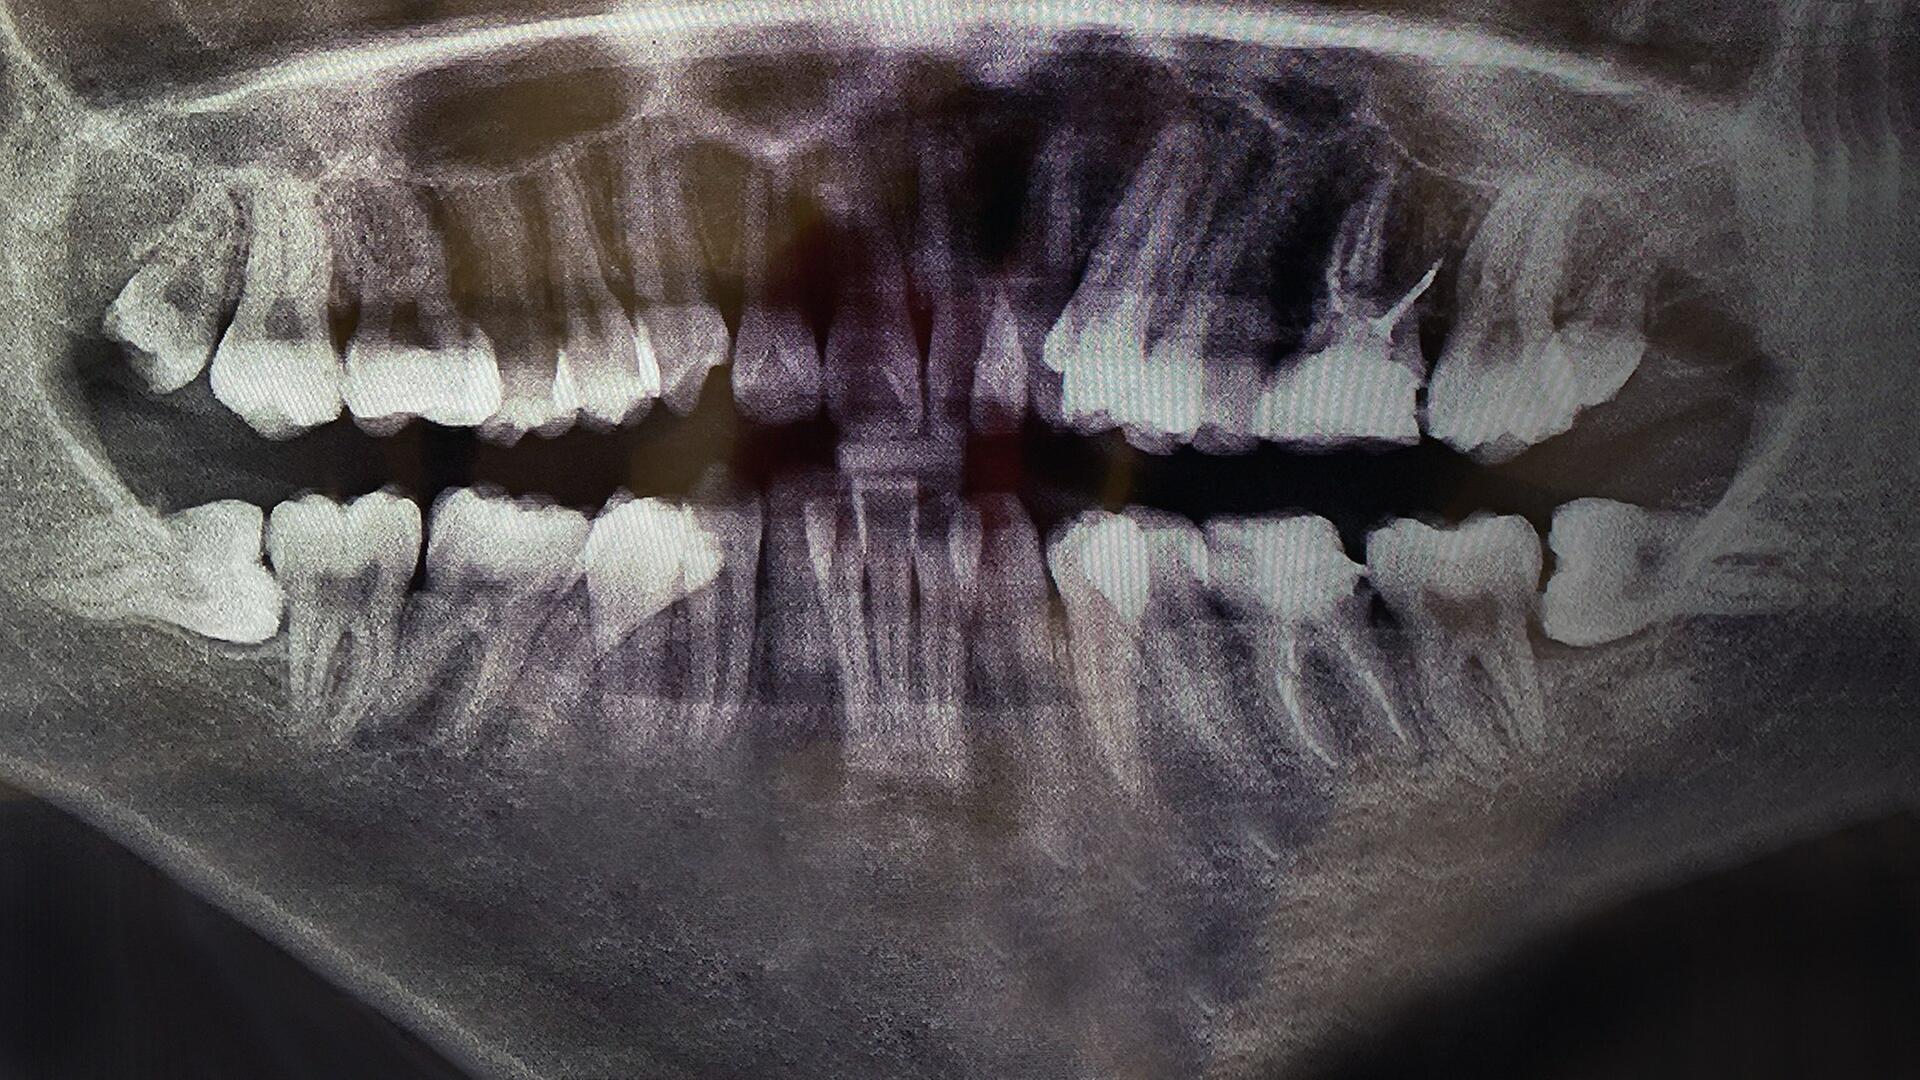

Der Weg zum Hollywood-Lächeln schien nie einfacher. Egal ob bei Facebook, Instagram oder auf Werbe-Plakaten: Überall wird es beworben. Doch schiefe Zähne begradigen, das konnten früher nur Kieferorthopäd*innen. Nun scheint es eine günstigere Alternative zu geben: Unternehmen versuchen mithilfe von riesigen Werbekampagnen, Kundinnen und Kunden für ihre neue Behandlungsmethode zu gewinnen - mit unsichtbaren Zahnschienen zum selber einsetzen. Wir haben uns das Geschäftsmodell und die Preise genauer angesehen und fragen: Dürfen die das?